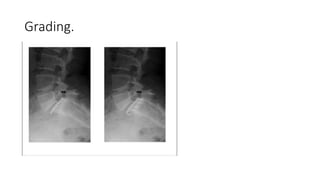

Spondylolisthesis

• Spondylolisthesis (also known as anterolisthesis) is defined as an

anterior displacement of a vertebra relative to the vertebra below,

whereas the reverse, i.e. when the superior vertebra slips posterior to

that below, is called retrolisthesis

(Butt and Saifuddin 2005).

Grading.